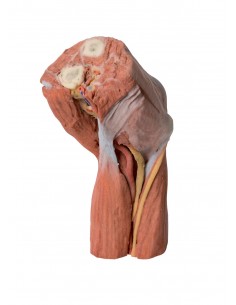

3D Anatomy 1.0 - Extremidades inferiores

Fosa poplítea con distal del muslo y pierna Erler Zimmer 3D anatomy Series MP1820